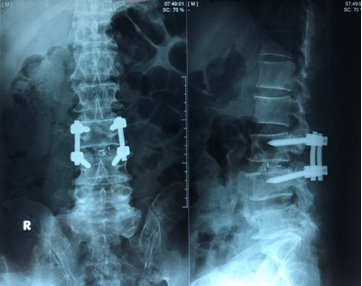

Tại thời điểm nhập viện, bệnh nhân có ý thức và mạch lạc. Các xét nghiệm cận lâm sàng bao gồm công thức máu cho thấy hồng cầu 3,7 T/l, bạch cầu 8,52 G/l, tiểu cầu 188 G/l, tổng phân tích nước tiểu, chức năng gan và thận, với mức triglyceride, cholesterol và axit uric bình thường. Creatinine huyết thanh 6,2 umol/L, ure huyết thanh 8,3 mmol/L. Chụp MRI (Hình 1) giảm tín hiệu nước các tầng đĩa đệm từ ngang mức L3. Tầng L3/L4: thoát vị rộng ra sau hướng xuống làm hẹp nặng ống sống (độ C), hẹp lỗ liên hợp hai bên, chèn ép chùm đuôi ngựa và rễ thần kinh tương ứng hai bên trong ống sống và ngách bên. Tầng L4/L5; phình đĩa đệm, chèn bao màng cứng làm hẹp ống sống (độ B), hẹp lỗ liên hợp bên trái, chưa thấy rõ chèn rễ thần kinh. Tầng L5/S1: thoát vị đĩa đệm trung tâm và cận phải, chèn ép bao màng cứng, chèn ép rễ thần kinh tương ứng bên phải đoạn trong ống sống. Bệnh nhân được chẩn đoán là hội chứng chùm đuôi ngựa và được lên lịch phẫu thuật mở bản sống rộng rãi, giải áp đoạn L3-L4, và cố định cột sống bằng vít qua cuống L3-L4 (Hình 2). Hậu phẫu không có biến chứng gì, bệnh nhân được xuất viện sau 10 ngày với cơ lực 2 chân được phục hồi, tuy nhiên rối loạn chức năng cơ vòng chưa cải thiện bệnh nhân được hướng dẫn đạt thông tiểu ngắt quãng. Sau 2 tháng, bệnh nhân tái khám với chức năng vận động được phục hồi gần như hoàn toàn, còn cảm giác căng tiểu và cảm giác đại tiện cải thiện rõ rệt với bệnh nhân có thể đại tiểu tiện được sau 3 tháng.

Hình 2. Phẫu thuật mở rộng ống sống L3-L4 giải áp và cố định cột sống bằng vít qua cuống lối sau